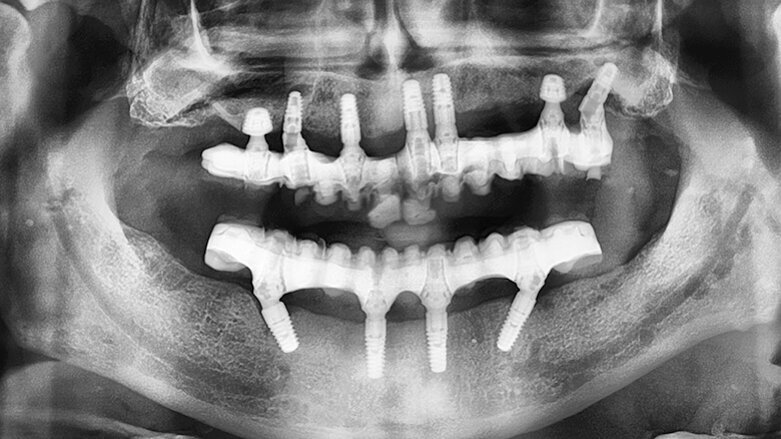

Panoramatický snímek zubů zachycující implantáty v dobré pozici. Ultrakrátké implantáty byly zavedeny v dobrém vztahu k čelistním dutinám, ale byly obklopeny malým množstvím kosti. (fotografie: dr. Ghirlanda)

Panoramatický snímek zubů zachycující implantáty v dobré pozici. Ultrakrátké implantáty byly zavedeny v dobrém vztahu k čelistním dutinám, ale byly obklopeny malým množstvím kosti.

Následně byl odklopen mukoperiostální lalok v rozsahu celého horního oblouku. Byl proveden pečlivý „debridement“, při němž byly odstraněny všechny zánětlivé a fibrózní tkáně a obnaženy všechny kostní defekty. Následně byly pomocí kostních dlátek a kulatých frézek vytvarovány mělké kostní defekty, zatímco hluboké defekty byly vyplněny xenoštěpem (Geistlich Bio-Oss, Geistlich Biomaterials) a překryty vstřebatelnou membránou (Geistlich Bio-Gide, Geistlich Biomaterials). Ve frontálním úseku byly zavedeny standardní implantáty (blueSKY, bredent medical), a zároveň byly v místech prvních molárů umístěny dvě fixtury 5,2 × 6,0 mm (copaSKY, bredent medical) (obr. 5). Z důvodu maximalizace primární stability ultrakrátkých implantátů byla zvolena vnitřní osteotomie k bikortikálnímu ukotvení implantátů. Fixtury nepronikly do sinu, ani nebyla patrná elevace sliznice sinu. Všechny implantáty dosahovaly primární stability ≥ 35 Ncm. Panoramatický RTG snímek pořízený na konci chirurgického zákroku prokázal správné umístění implantátů (obr. 6).